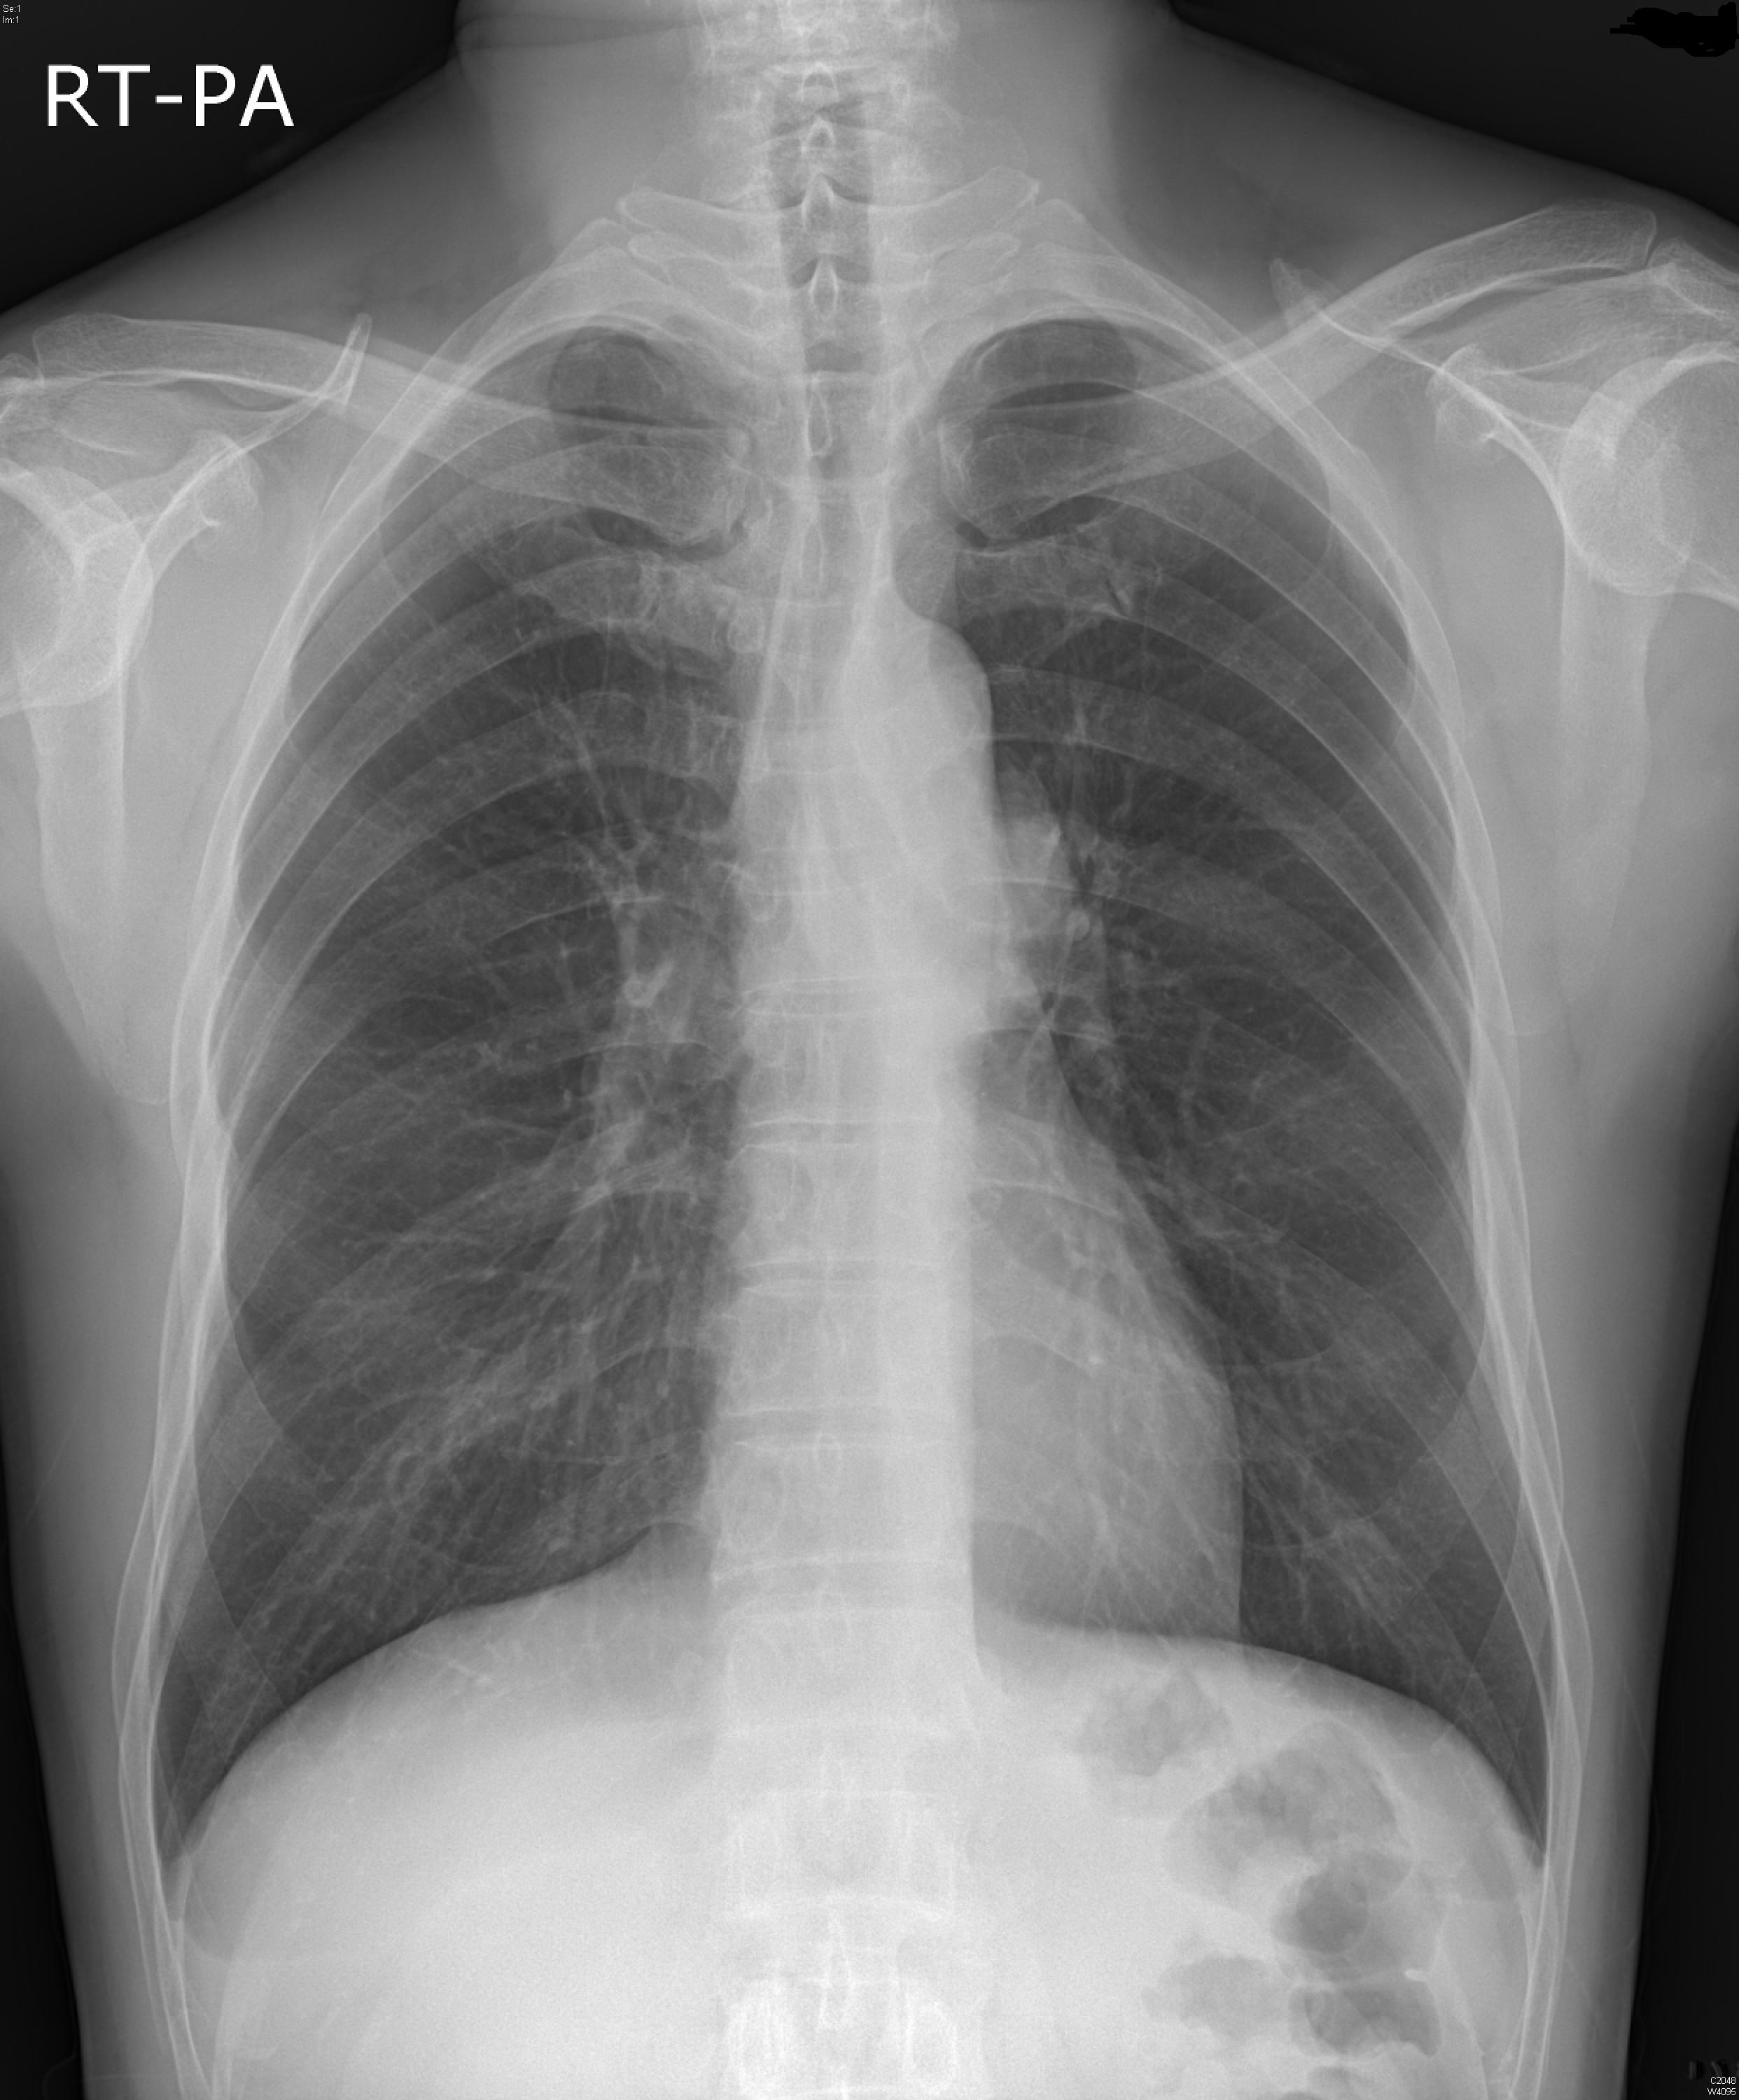

M/56

4°³¿ù ÀüºÎÅÍ ¹ß»ýÇÑ Èí±â½ÃÀÇ ÈäÅë

±âħ °¡·¡ ÀÖÀ½

5ÀÏ ÀüºÎÅÍ ¾ÇÈ­µÇ¾î ³»¿øÇÔ

2012³â 11¿ù Chest PA, lateral

2013³â 5¿ù Chest PA, lateral ÀÔ´Ï´Ù.